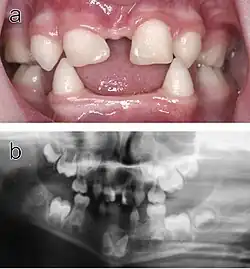

- Zawiązek zęba 38

Częściowo zatrzymany ząb 48